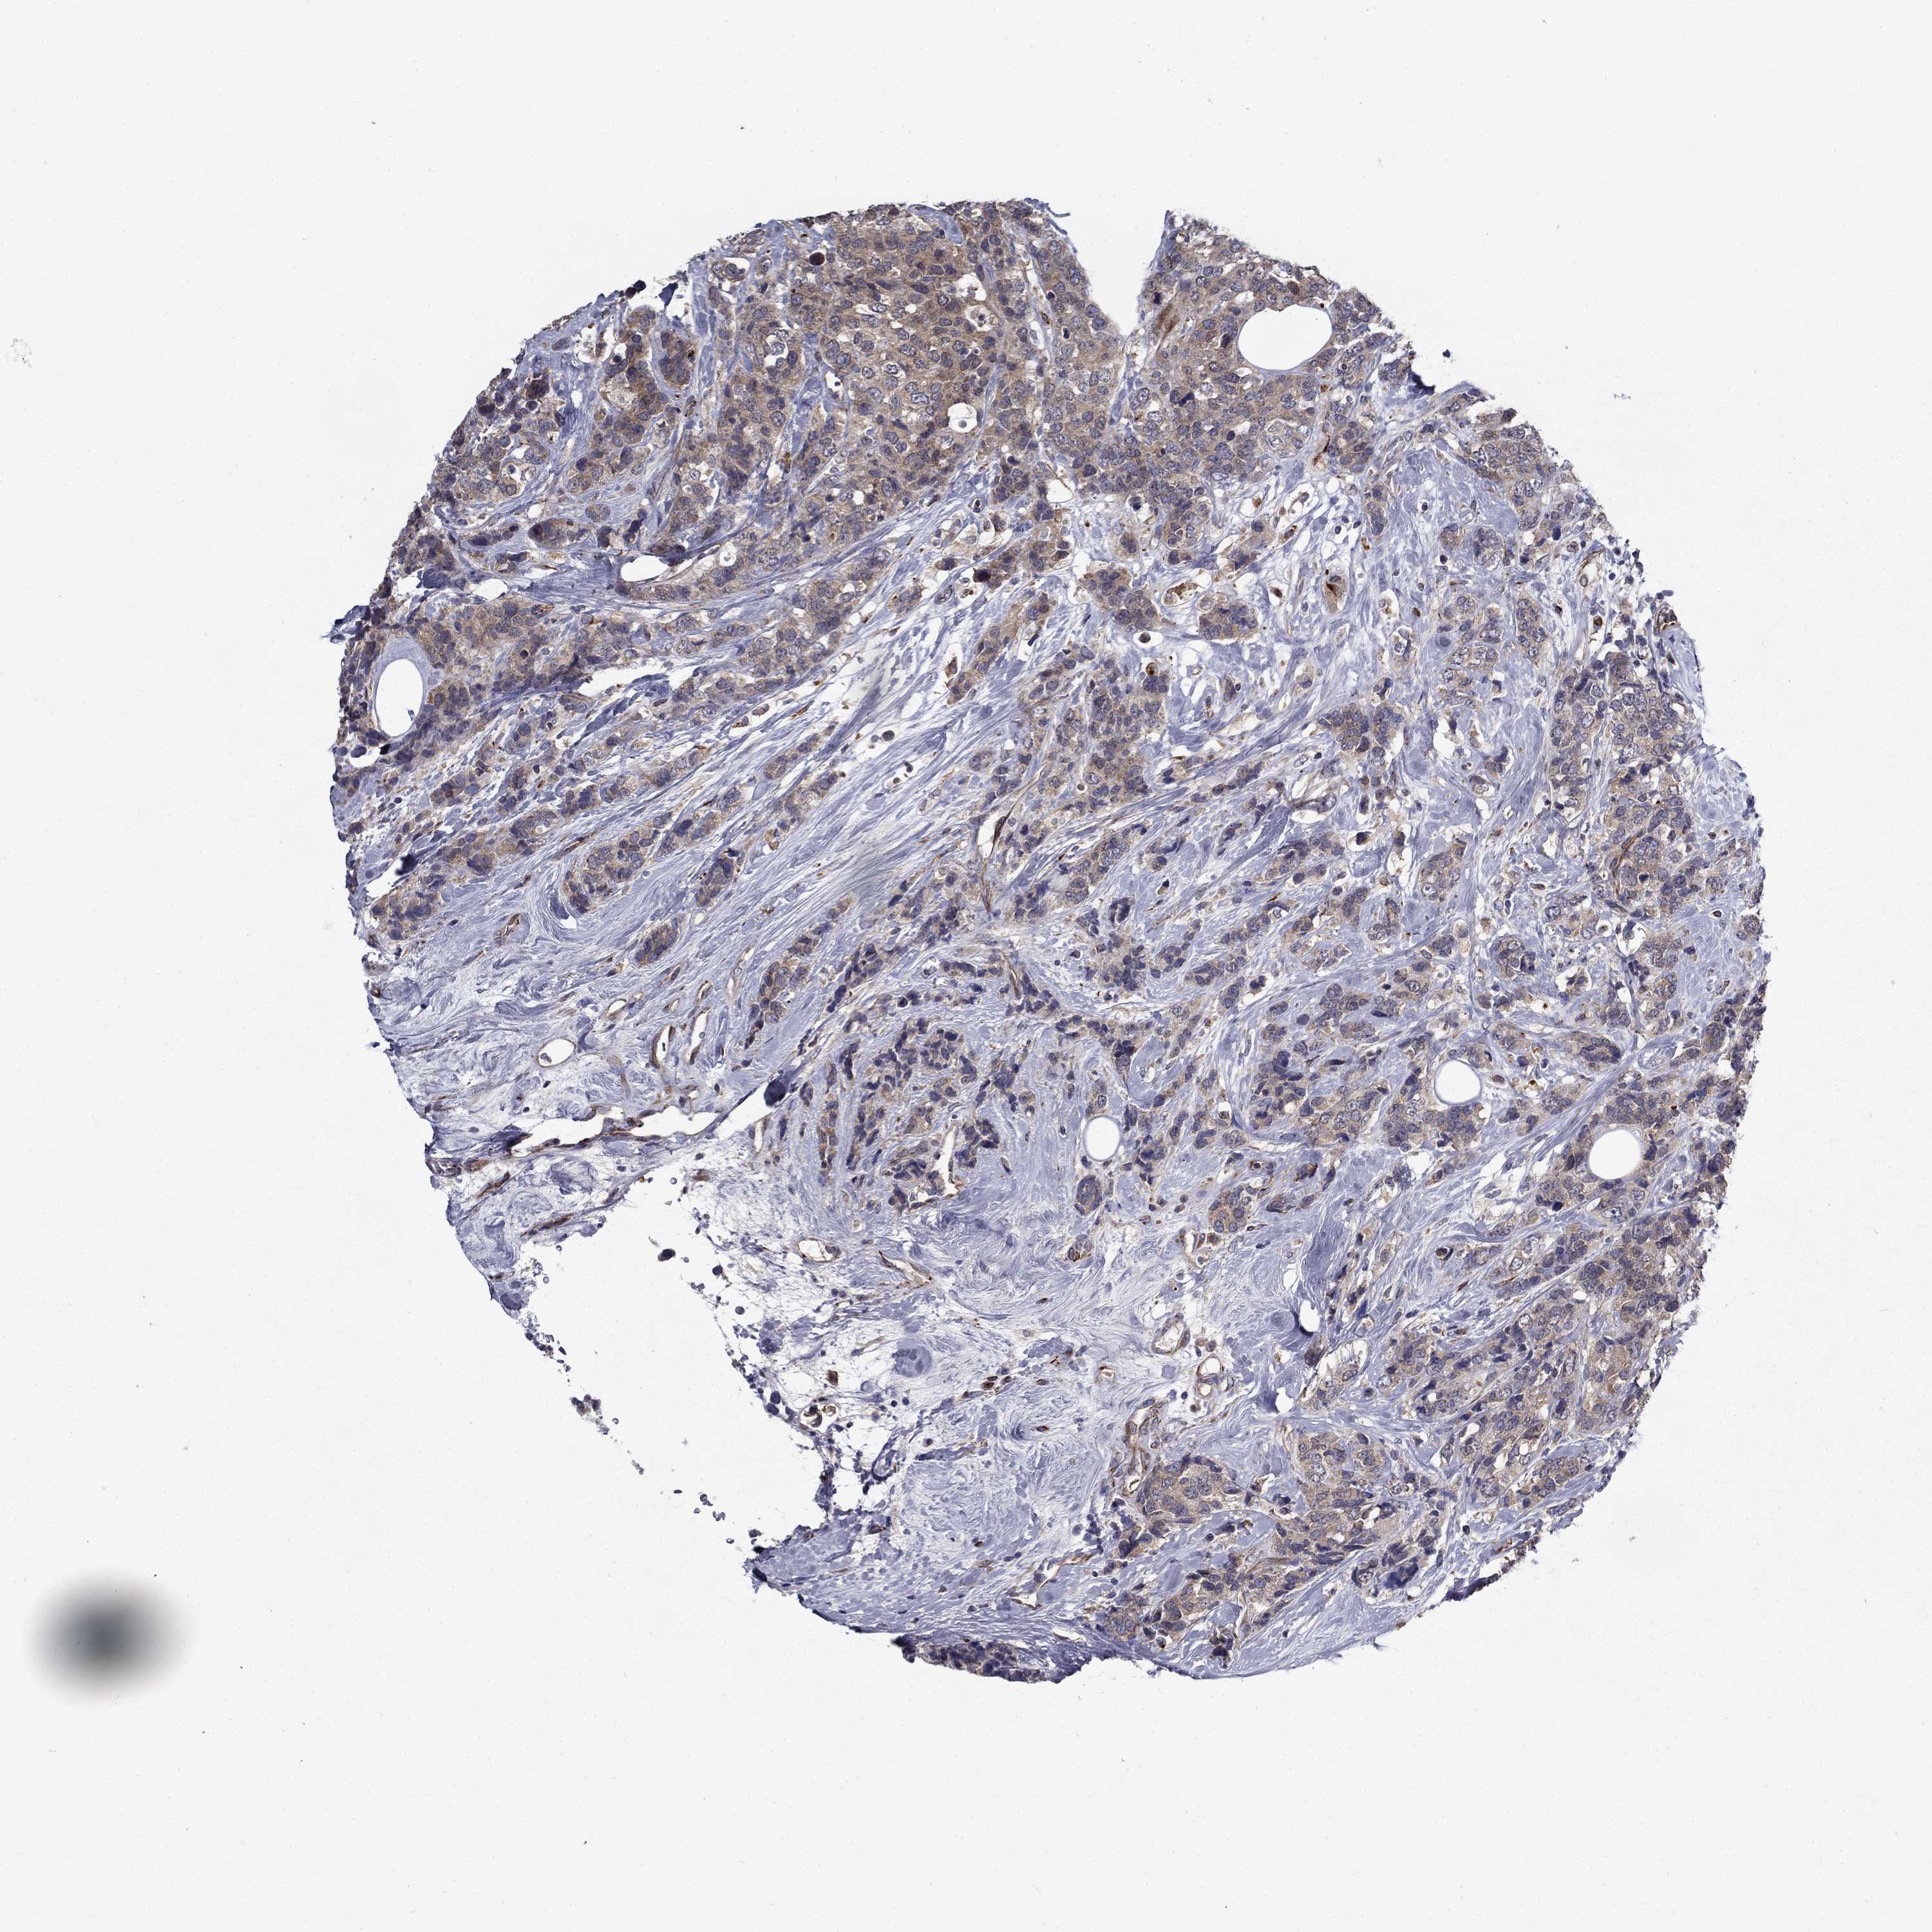

BRCA TCGA BRCA VALIDATION PROTEIN EXPRESSION